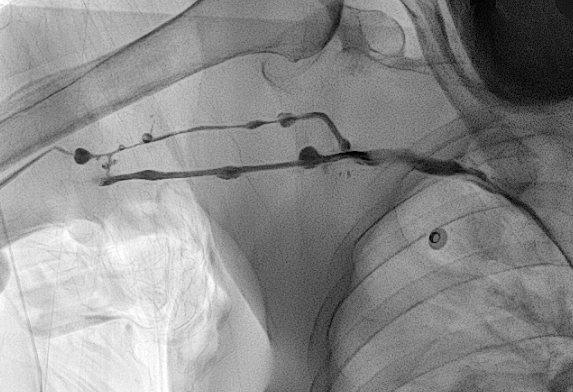

b. 혈관이 막혔거나 아주 좁은 경우

오랜 기간 동안 PICC 를 가지고 계셨거나, 독한 약물 치료를 받으신 분들 중에는 말초 정맥이 막혀버렸거나 아주 좁아져버린 분들이 계십니다. 이 경우 찔렀던 혈관을 그대로 이용하려면 풍선 카테터를 이용하여 혈관성형술을 하거나, 아니면 다른 혈관을 새로 찔러 들어가야 합니다. 두 해결 방법 모두 시간을 늘어지게 하는 방법이지요.